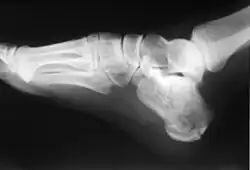

Calcaneus fracture X-ray

Normally the tibia sits vertically above the calcaneus (pes rectus). If the calcaneal axis between these two bones is turned medially the foot is in an everted position (pes valgus), and if it is turned laterally the foot is in an inverted position (pes varus).[5]